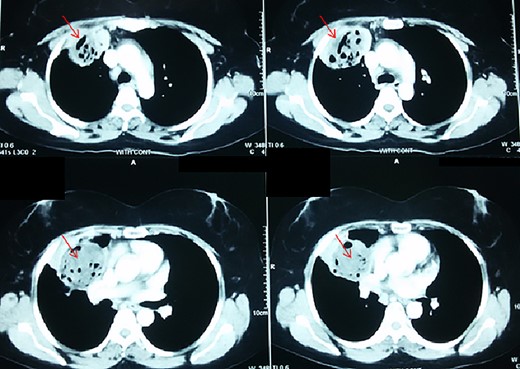

Chest X-ray (CXR) showed a heterogeneous density with irregular margins in the right lung (Fig. 1). CT scan demonstrated a heterogeneous mass that measured 5.5 × 6 × 7.8 cm with irregular thick margins. The mass was anteriorly located in the upper lobe of the right lung with air bubbles and necrosis (Fig. 2). Two lymphadenopathies were observed that measured around 2 cm each; one of which was in the hilum of the right lung and the other was located inferior to the right main bronchus. No other lesion was detected elsewhere. PET scan was also suggestive of malignancy as it demonstrated a heterogeneous mass with irregular margins which had irregular enhancement in the peripheral, suggesting hyper metabolic retention. The standardized uptake values (SUV) of the mass ranged between 4 and 7 with central necrosis and multiple gas bubbles. Multiple lymphadenopathies were also observed with different sizes ranged from 10 to 20 mm with SUVmax reaching 7 (Fig. 3). Bronchoscopy found an erythematous and oedematous opening of the anterior segment of the right upper lobe of the lung and epithelial dysplasia was found with bronchial lavage (BAL), but endobrachial biopsy was not conclusive.

Thoracic CT-scan with the heterogenous mass having necrosis and gas bubbles (arrows).